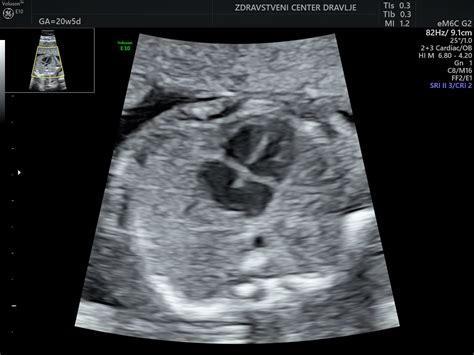

V enaindvajsetem tednu ima plod še vedno dovolj prostora za prosto premikanje po maternici. Velik je približno 26 centimetrov in težak dobrih 300 gramov. V tem času ginekologi pogosto opravijo podroben ultrazvočni pregled (morfologija ploda), kjer je možno izvedeti tudi spol otroka.

Dvaindvajseti teden prinaša oblikovanje obrvi nad očmi. Plod meri 28 cm in tehta od 330 do 370 gramov. Doseže razvojno stopnjo, ki mu daje majhno možnost preživetja v primeru prezgodnjega poroda. To je tudi čas za opravljanje ultrazvočnega pregleda morfologije ploda. Starši lahko že pričnejo božati otroka skozi trebuh in mu peti pesmice.